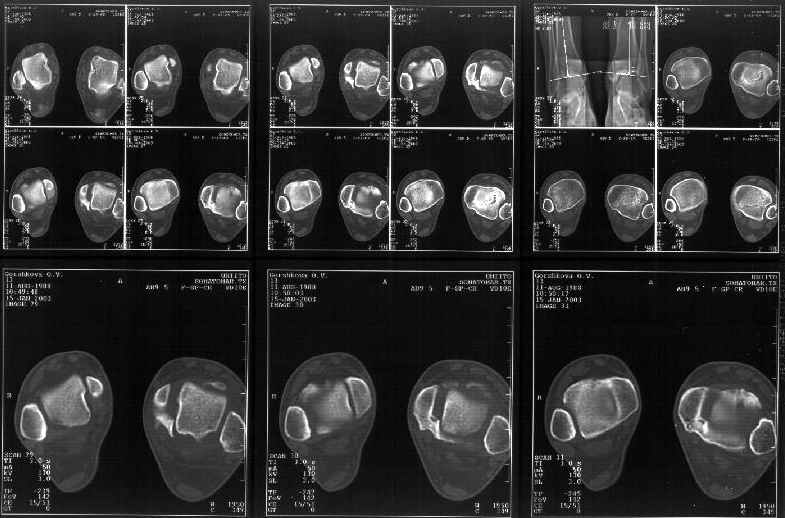

Сегодня пациентке сделали сравнительную КТ. А ксиальные и Фронтальные срезы приложены. Ваше мнение?

Аксиальные